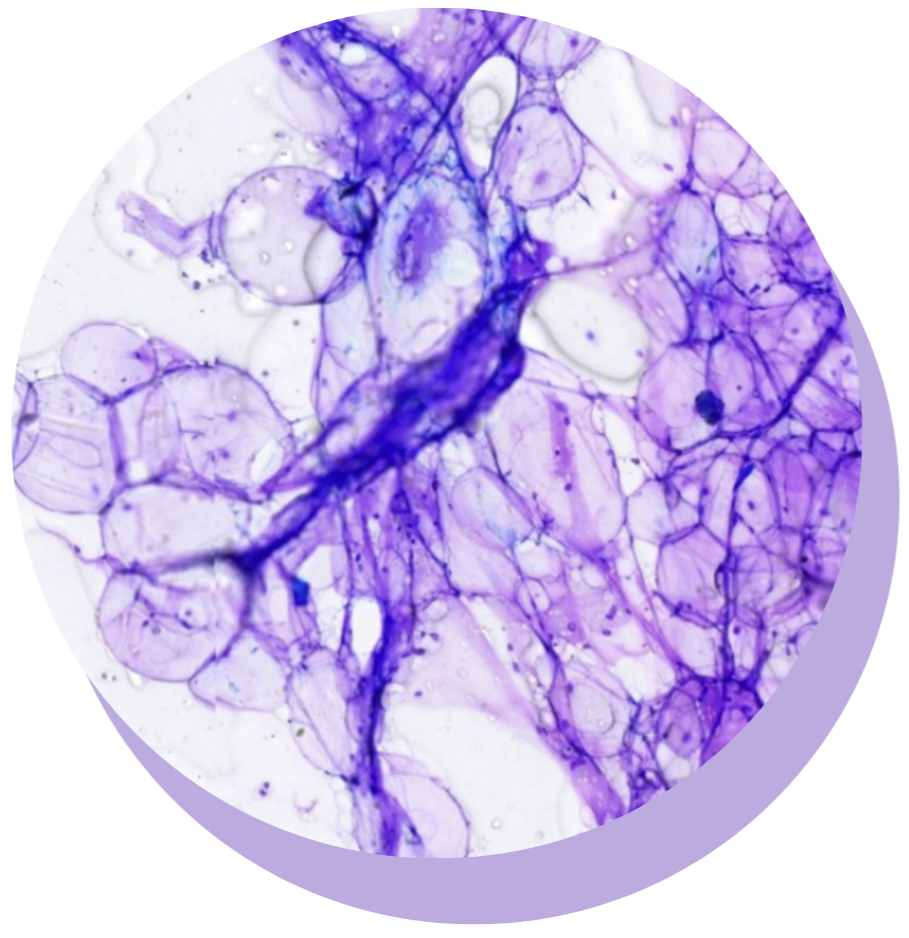

MASTERING CYTOLOGY: SKIN AND SUBCUTIS

Boost your confidence and skills in interpretation of fine-needle aspirate (FNA) cytology from masses/lesions in the skin and subcutis.